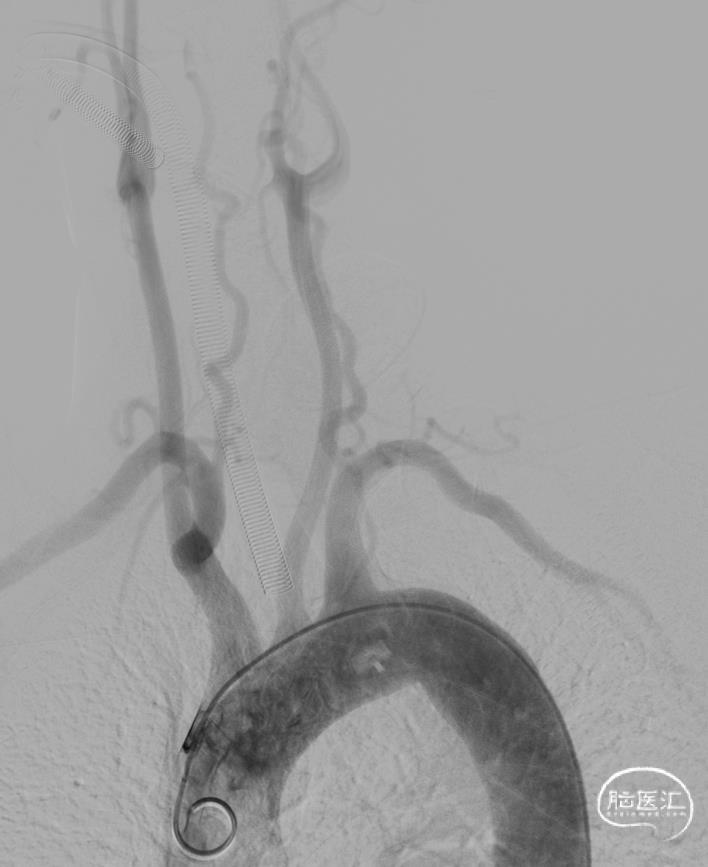

弓上造影:II型弓

支撑系统使用长鞘NeuronMax 6F / 通桥银蛇 6F。

II型弓,同轴系统直接到位困难。不巧的是,手术室所有径限的125cm MPA1导管均无货。

尝试用5F Ver到位后,交换260cm泥鳅导丝,顺利置入同轴系统。